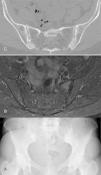

(A) Anteroposterior radiograph of pelvis showing calcification in fibrocartilage in the pubic symphysis, as well as sclerosis in both sacroiliac joints with cortical irregularity. (B) Axial slice of magnetic resonance of the pelvis. Short-tau inversion recovery (STIR) sequence, with hyperintense signal in both sacroiliac joints. (C) Computed tomography, axial image, of pelvis, showing the vacuum phenomenon in right sacroiliac joint, as well as calcification in fibrocartilage of both sacroiliac joints, with osteophytes.

We report the case of a 50-year-old woman who presented with a 3-month history of inflammatory low back pain and arthritis of the knees, with no other type of manifestations. Laboratory analyses demonstrated an elevated C-reactive protein level (2.5mg/dL) and erythrocyte sedimentation rate (43mm/h) and she was found to be negative for human leukocyte antigen (HLA) B27; there were no other abnormal findings. In the initial radiological study, plain radiography demonstrated meniscal calcification in both knees and sclerosis in both sacroiliac joints; magnetic resonance imaging (MRI) showed bone marrow edema in a short-tau inversion recovery (STIR) sequence (Fig. 1A and B). We observed no syndesmophytes affecting the axial skeleton. These findings led us to consider a differential diagnosis including spondyloarthritis (SpA) and pyrophosphate arthropathy. There were rectangular extracellular crystals with positive birefringence in synovial fluid obtained from knee. We requested computed tomography (CT) of the sacroiliac joints (Fig. 1C), which showed sclerosis with linear intra-articular calcifications in both joints. The patient was diagnosed with arthritis caused by calcium pyrophosphate deposition. Treatment was begun with low-dose steroids and colchicine, and the symptoms improved.